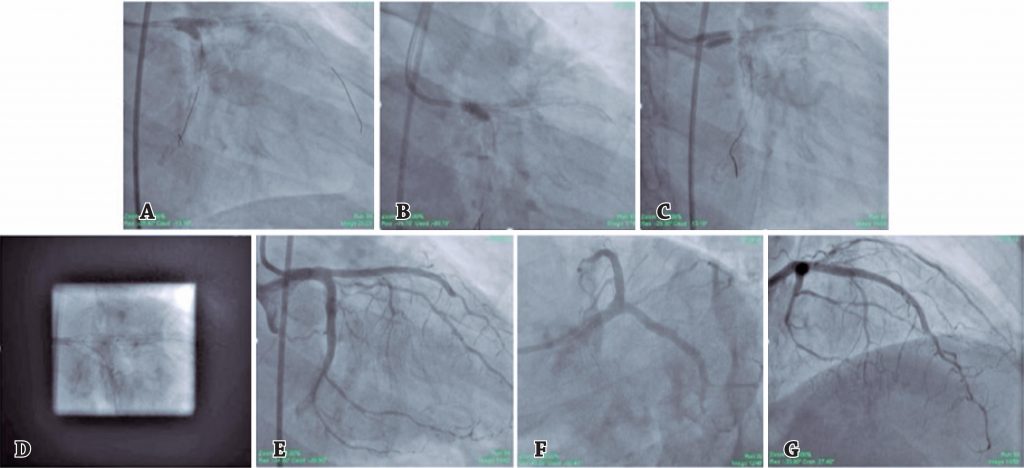

Stenting of left main bifurcation lesion using modified double-kissing culotte technique

Left main coronary artery bifurcation represents one of the most challenging settings for the interventional cardiologists. The conventional stents are designed and shaped to restore tubular geometry, while the left main coronary artery bifurcation is far more complex with different diameters and non-tubular cross-sections. In relevant patients, two stent strategy is preferred over provisional T-stenting. The double-kissing crush has been the preferred double stent technique. We present a case in which the double-kissing approach was used in left main coronary artery bifurcation stenting with the culotte technique, which resulted in good angiographic outcome and no malapposition. Patient was stable even at 4 months follow-up.